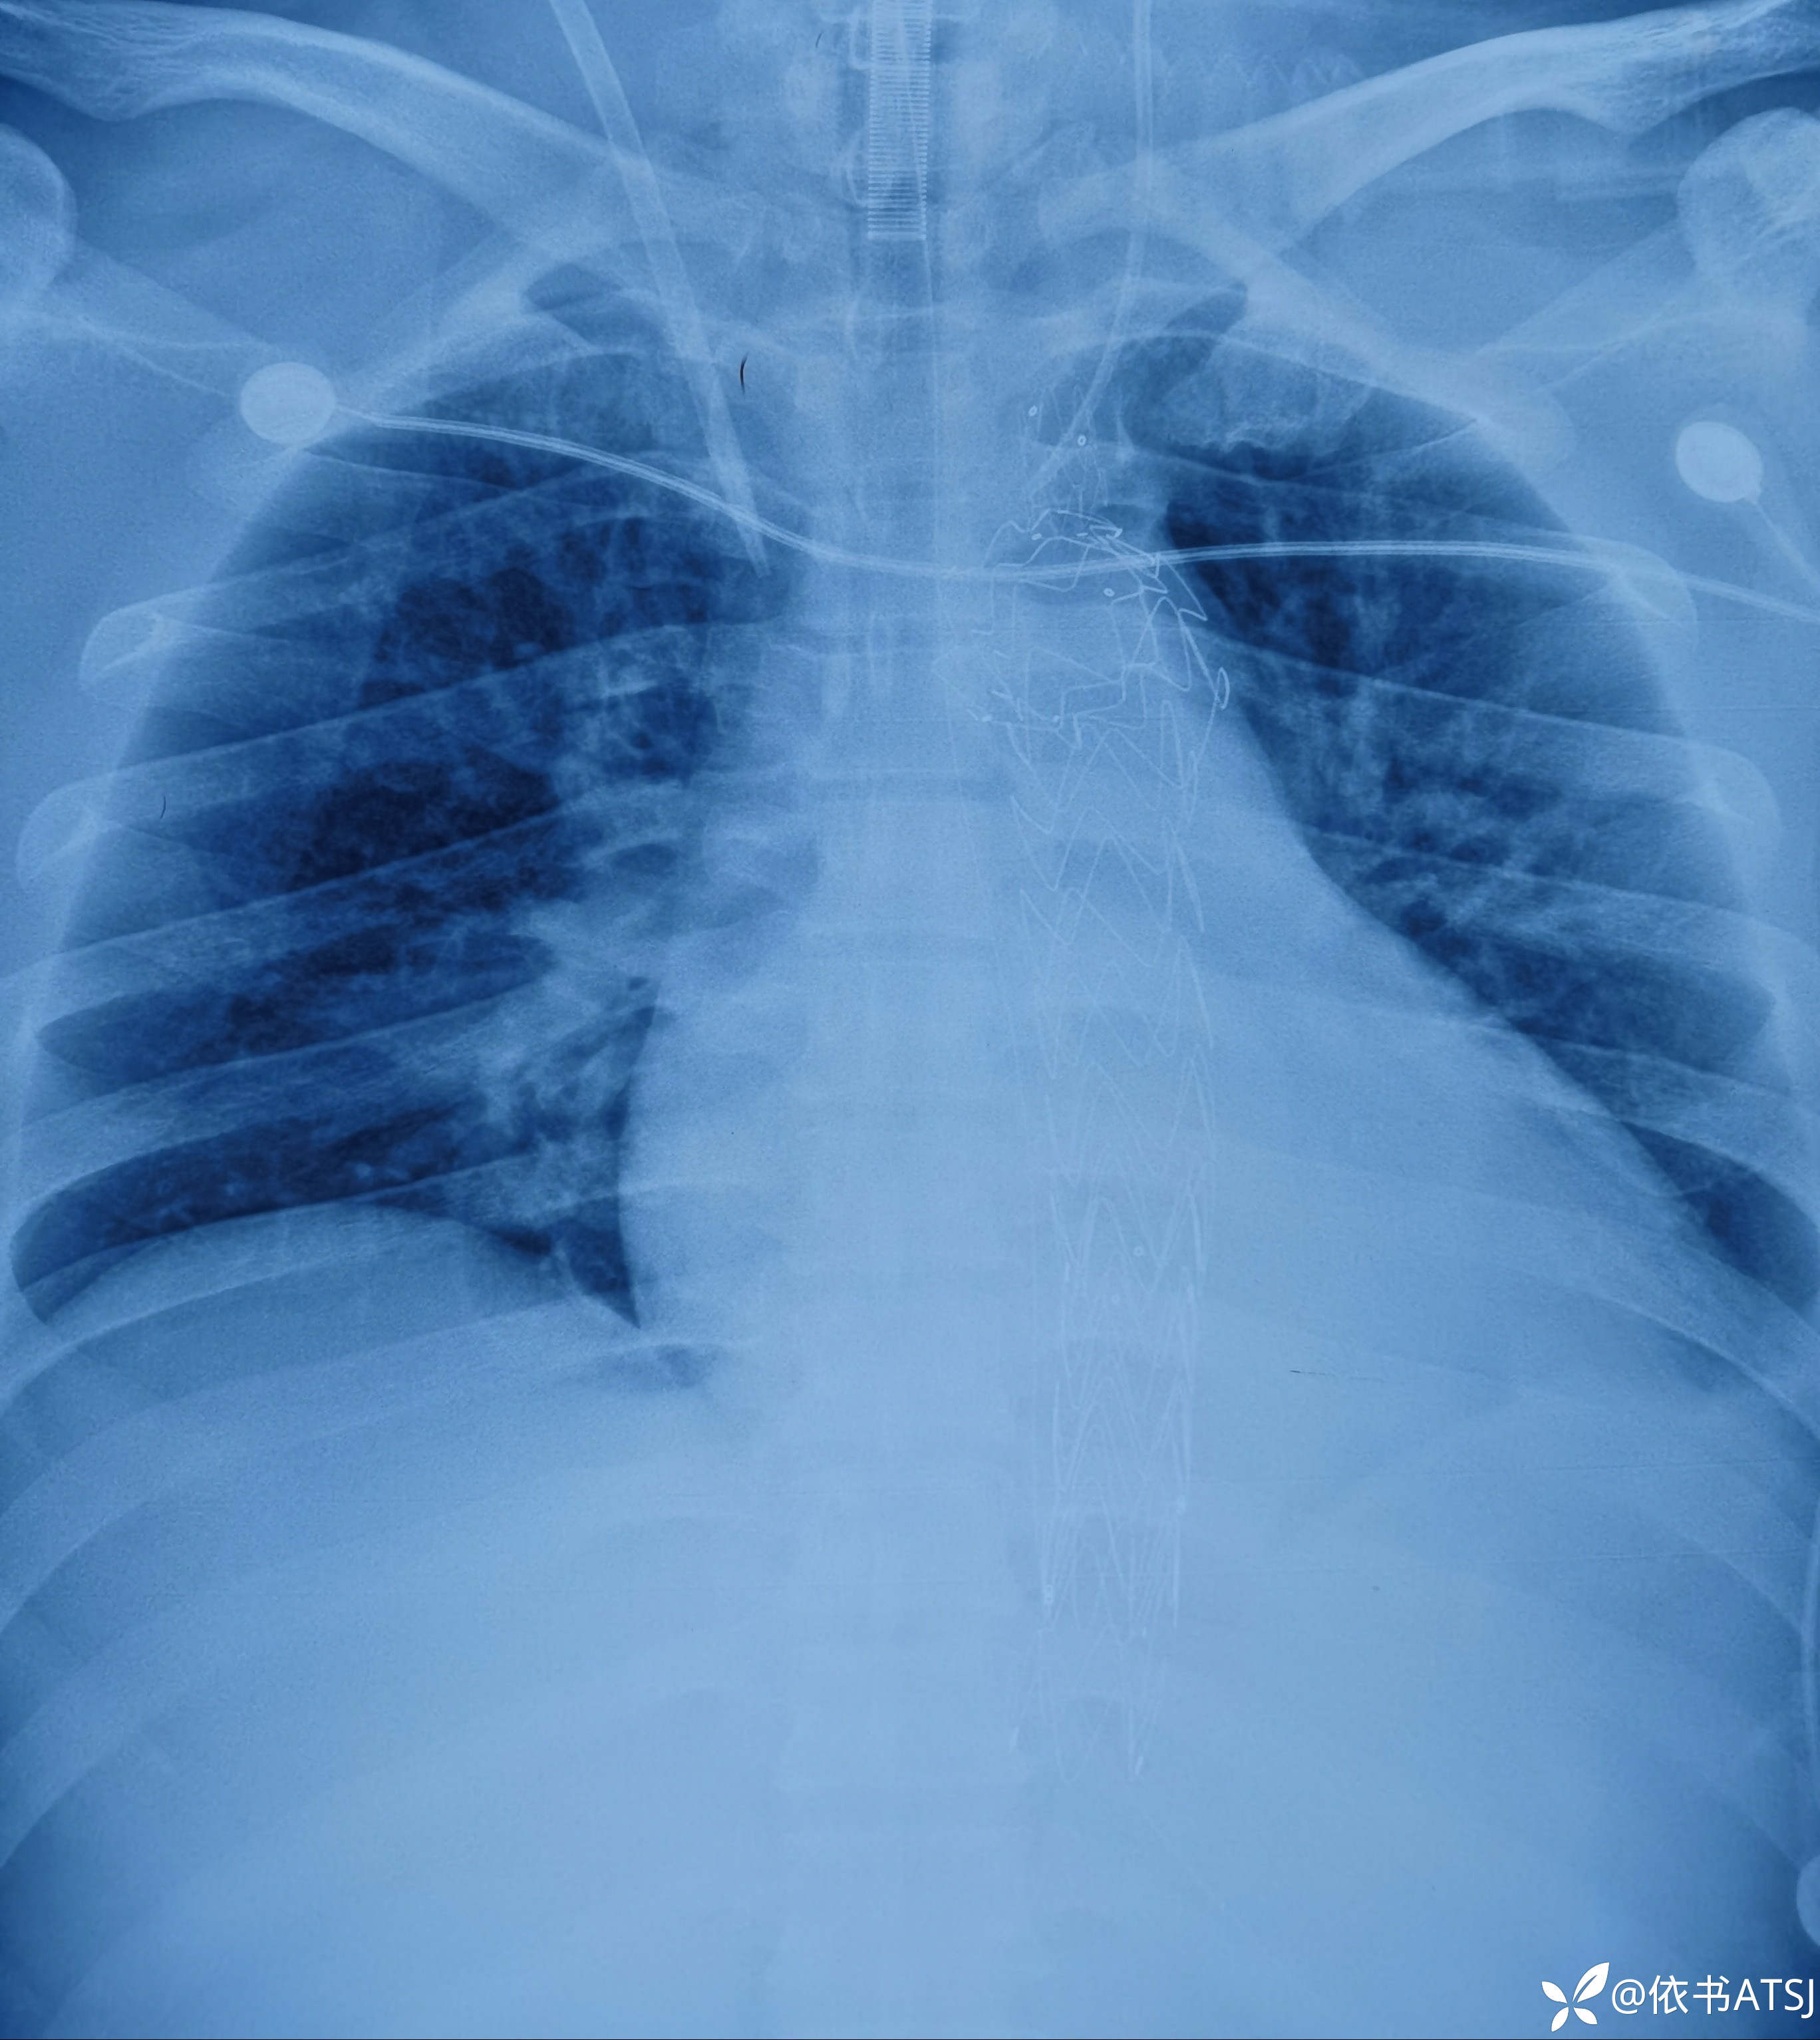

升主动脉-腹主动脉全程增粗,多个破口,累及肠系膜动脉、髂总动脉、髂内髂外动脉

讨论:本例患者,34岁,体型肥胖,高血压3年余,未重视,未系统诊治,突发胸腹部疼痛入院,虽然放了根长长的支架,命保住了,尿量也不错,可是血肌酐高,短期内脱离不了透析,针对这一年轻患者的全程广泛主动脉撕裂、多个破口,各位老师,您认为非常有必要排查血管炎这一疾病吗?